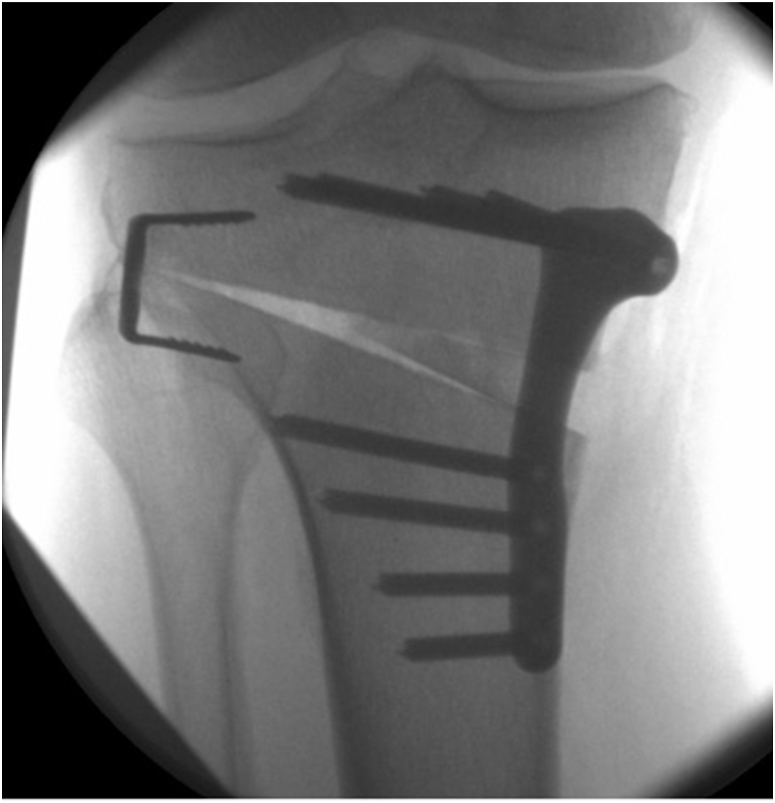

With the recent utilization of a ‘hinge wire’ to protect the hinge intra-operatively during opening of the osteotomy, a screw can be positioned over the wire to compress the hinge once satisfactory opening has been achieved and held with a fixed angle locking plate. Fig. 7, Fig. 8 demonstrates a cannulated head compression screw with a variable pitched thread. Biomechanical studies have demonstrated this to help resists axial and torsional forces in HTO.30

Fig. 7.

Anteroposterior radiograph showing the hinge screw across the hinge point.

5.7. Hinge staple

Intra-operatively a Type 1 hinge fracture may be identified, that extends in line with the primary osteotomy. While these may be compressed indirectly through the plate using a non-locking screw, another option may be to use a Nitinol compression staple across the hinge point through a separate incision on the lateral side and under image intensifier guidance (Fig. 9, Fig. 10). The compression staple gives immediate compression across the fracture and can be tested intra-operatively by stressing the hinge point with a varus force.

Fig. 9.

Antero-posterior image intensifier view of the high tibial osteotomy with provisional positioning of the staple.

Fig. 10.

Antero-posterior image intensifier view of the high tibial osteotomy with final positioning of the staple with compression across the hinge.

5.9. Fixation

Once the desired correction has been achieved, fixation can be performed in the standard fashion with an anatomical locking plate. The authors’ choice of implant is the ACTIVMOTION high tibial osteotomy plate (Newclip Technics®, Haute-Goulaine, France) (Fig. 7, Fig. 8, Fig. 9, Fig. 10). Other popular options include the TomoFix® Medial High Tibia Plate (Synthes GmbH, Solothurn, Switzerland) which is a locking compression plate and the Tibia Opening Wedge Osteotomy Plate (Arthrex Inc., Naples, Florida, USA), also known as the Puddu Plate, which uses a stainless-steel plate with a metallic block incorporated which props the distracted medial cortex of the tibia.